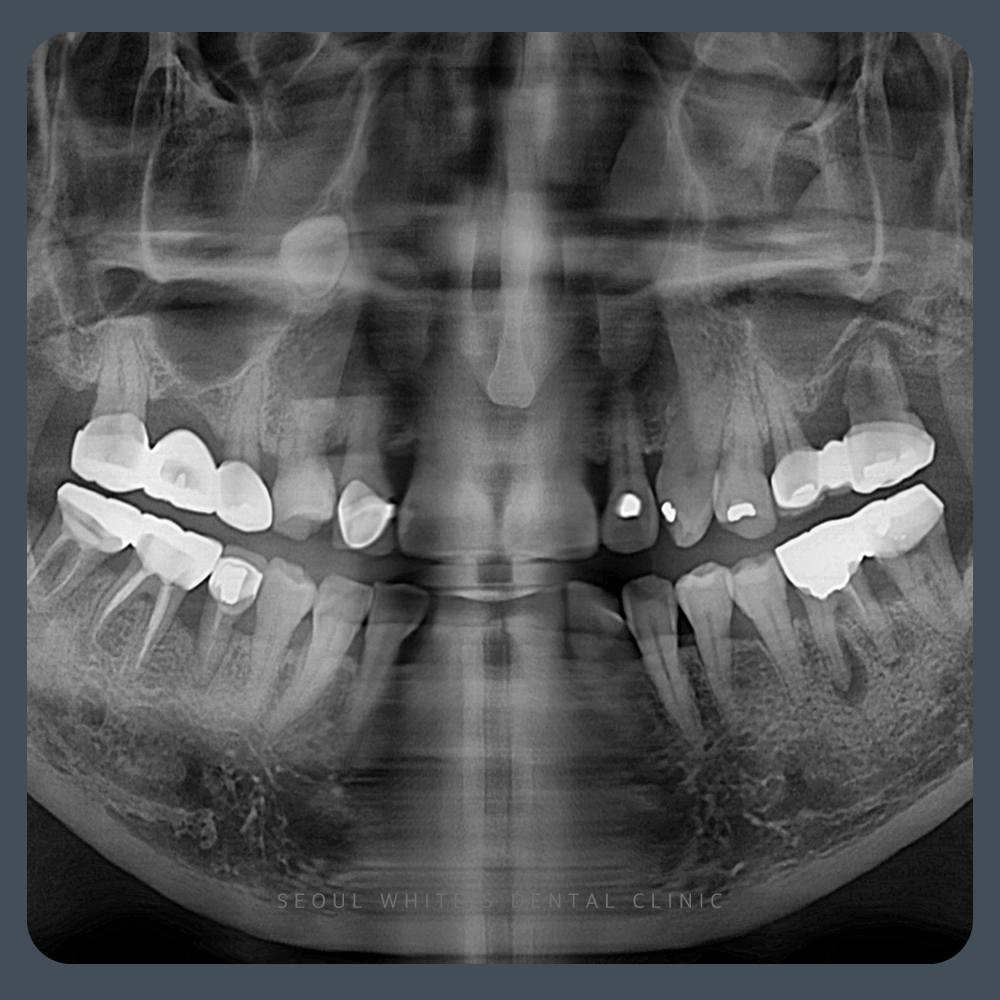

환자분은 상악 구치부가 심하게 골소실이 발생한 상태였습니다. 치주 질환으로 인해 상악의 골 흡수가 심해진 경우였으며, 치아 상실 후 시간이 많이 경과하여 상악동 근처의 뼈 높이가 부족해졌습니다.